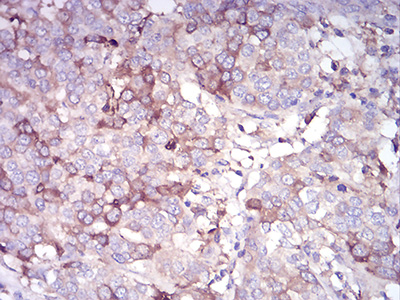

图片:

Immunohistochemical analysis of paraffin-embedded human bladder cancer tissue using anti-CDH11 antibody. Counter stained with hematoxylin.